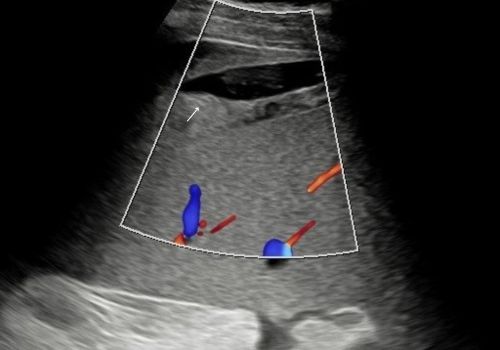

Figure 5 and 6 above; Heterogeneous area adjacent to the spleen with fluid demonstrates no colour doppler flow (arrow).

A heterogenous area with a small area of central fluid left subphrenic space surrounding/indistinct from the superior spleen was identified with no colour doppler flow.

Figure 2, 3 and 4 above; Heterogeneous area(star) with a small area of central fluid in the left subphrenic space surrounding and indistinct from the spleen (arrow)